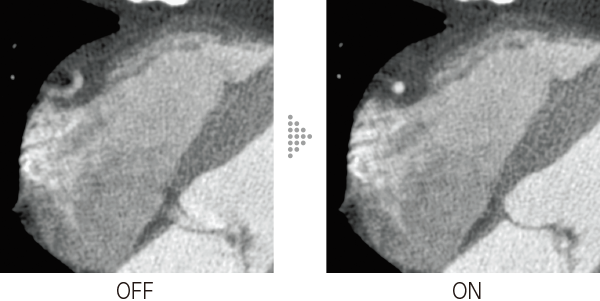

In cardiac CT examinations, the various factors such as heart rate and heart movement affect image quality. With conventional image reconstruction methods, unfocused coronary arteries and artifacts caused by motion could occur, resulting in images not meeting the expected quality, which could affect the diagnosis. To help resolve these problems, Fujifilm developed Cardio StillShot, which calculates the direction and amount of movement of the subject in four dimensions based on RawData collected during cardiac CT examinations, and corrects it during image reconstruction to achieve an effective temporal resolution of up to 28 msec.*1

The effective time resolution contributes to improved diagnostic capability by providing high-definition focused clinical images with less motion artifacts even in patients with a high heart rate.